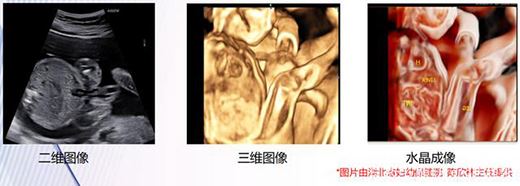

目前而言,二維超聲通過切面成像,仍然是超聲醫師的主要診斷途徑;三維、四維超聲通過

提供立體結構和動態圖像,成為重要的輔助診斷。

水晶成像CrystalVue技術為超聲診斷提供了全新的三維圖像,也為醫生提供了一個前所未有的超聲視角。

CrystalVue是一種全新的容積渲染成像方式。在三維成像基礎上,可同時顯示容積圖像的外部輪廓及內部結構,區分軟組織和骨結構,有多種模式可以更好的顯示不同軟組織和結構,進一步提升超聲掃查的精準度。

水晶成像:增強對比度,可更容易地區分不同回聲性質的組織;

反轉成像:原高回聲反轉后能夠清晰的將線狀腦溝顯示為暗線,原低回聲反轉后能使腦回區域顯示的更加明亮;

仿真成像:照明系統使顱腦表面凹凸不平的部分更加立體,正確傳遞皮質折疊程度的信息。